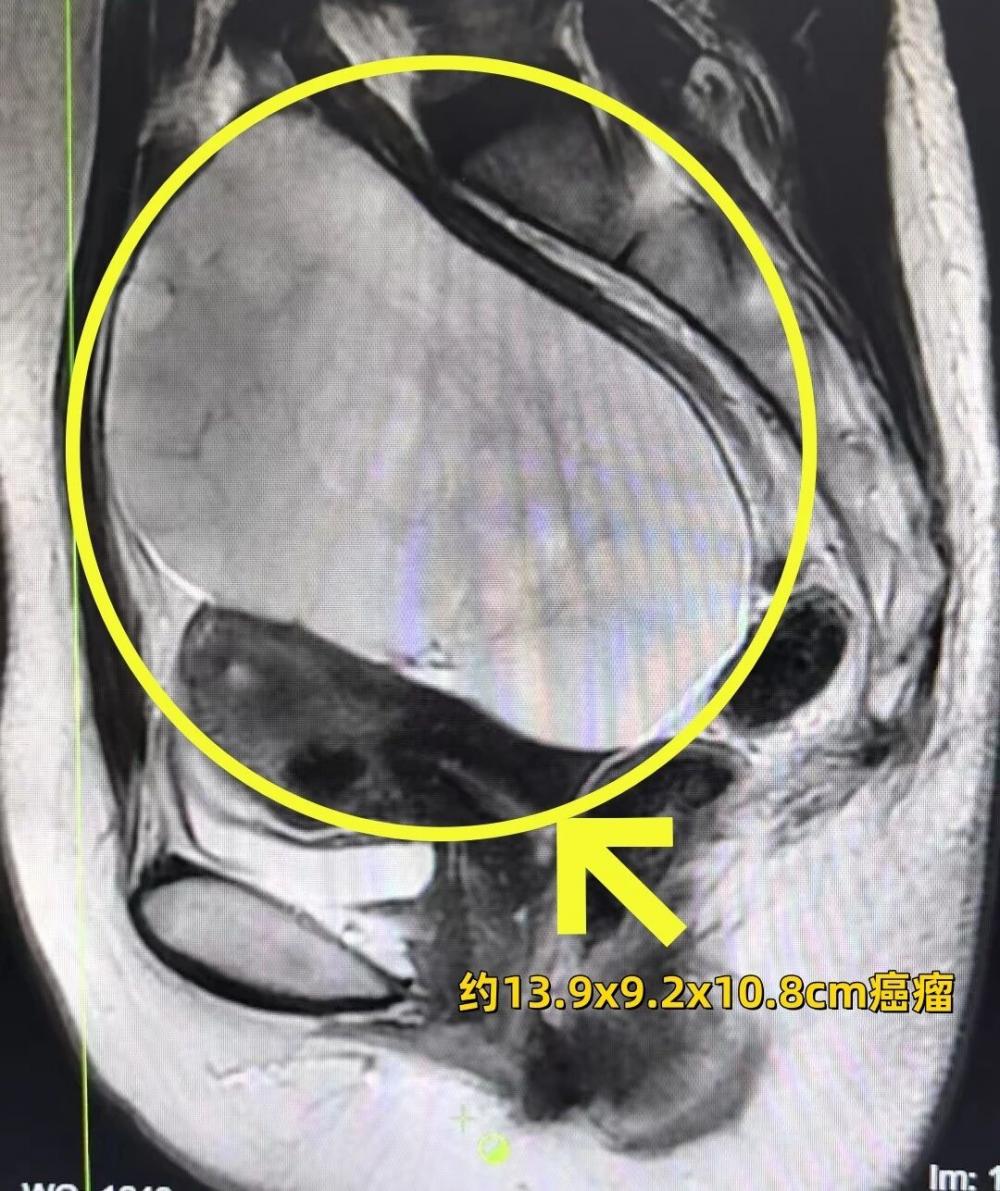

五年后,不断加重的尿频、腹部隐胀感让她无法再忽视。10月末,当鼓起勇气的她,找到徐州市妇幼保健院妇科肿瘤亚专科专家蔡莉,彩超结果却如晴天霹雳——盆腔里曾经的“小囊肿”疯狂繁殖,已变为直径13厘米的巨大包块!

手术台上,残酷的现实被快速病理结果又一次验证:卵巢癌。蔡莉主任立即为其实施了卵巢癌分期手术。术后病理显示为“卵巢粘液性肿瘤”。